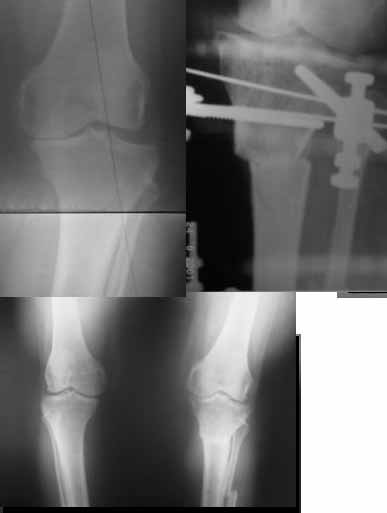

AC> Обратилась дама 25 лет. Вынуждена ходить в брюках из-за genu varum,

AC> что побудило обратиться за коррекцией.

Сейчас это модно (в смысле косметическая коррекция)... Хотя, судя по фото - в данном случае енто вполне оправдано...

Судя по снимку у девушки имеется внутренняя установка надколенников...

Как у нее с торсионным статусом? Бедро? Голень? КТ? Торсиометры? А то, куда будут

смотреть надколенники после вашей коррекции - тоже существенный

косметический момент. Или не так?

AVM> Судя по снимку у девушки имеется внутренняя установка надколенников...

AVM> Как у нее с торсионным статусом? Бедро? Голень? КТ? Торсиометры?

Похоже, немного есть. Думаю пренебречь.

Вот ещё картинки, которые отправлял в Ортопод. Коррекция кривизны и удлинение на 3 см.